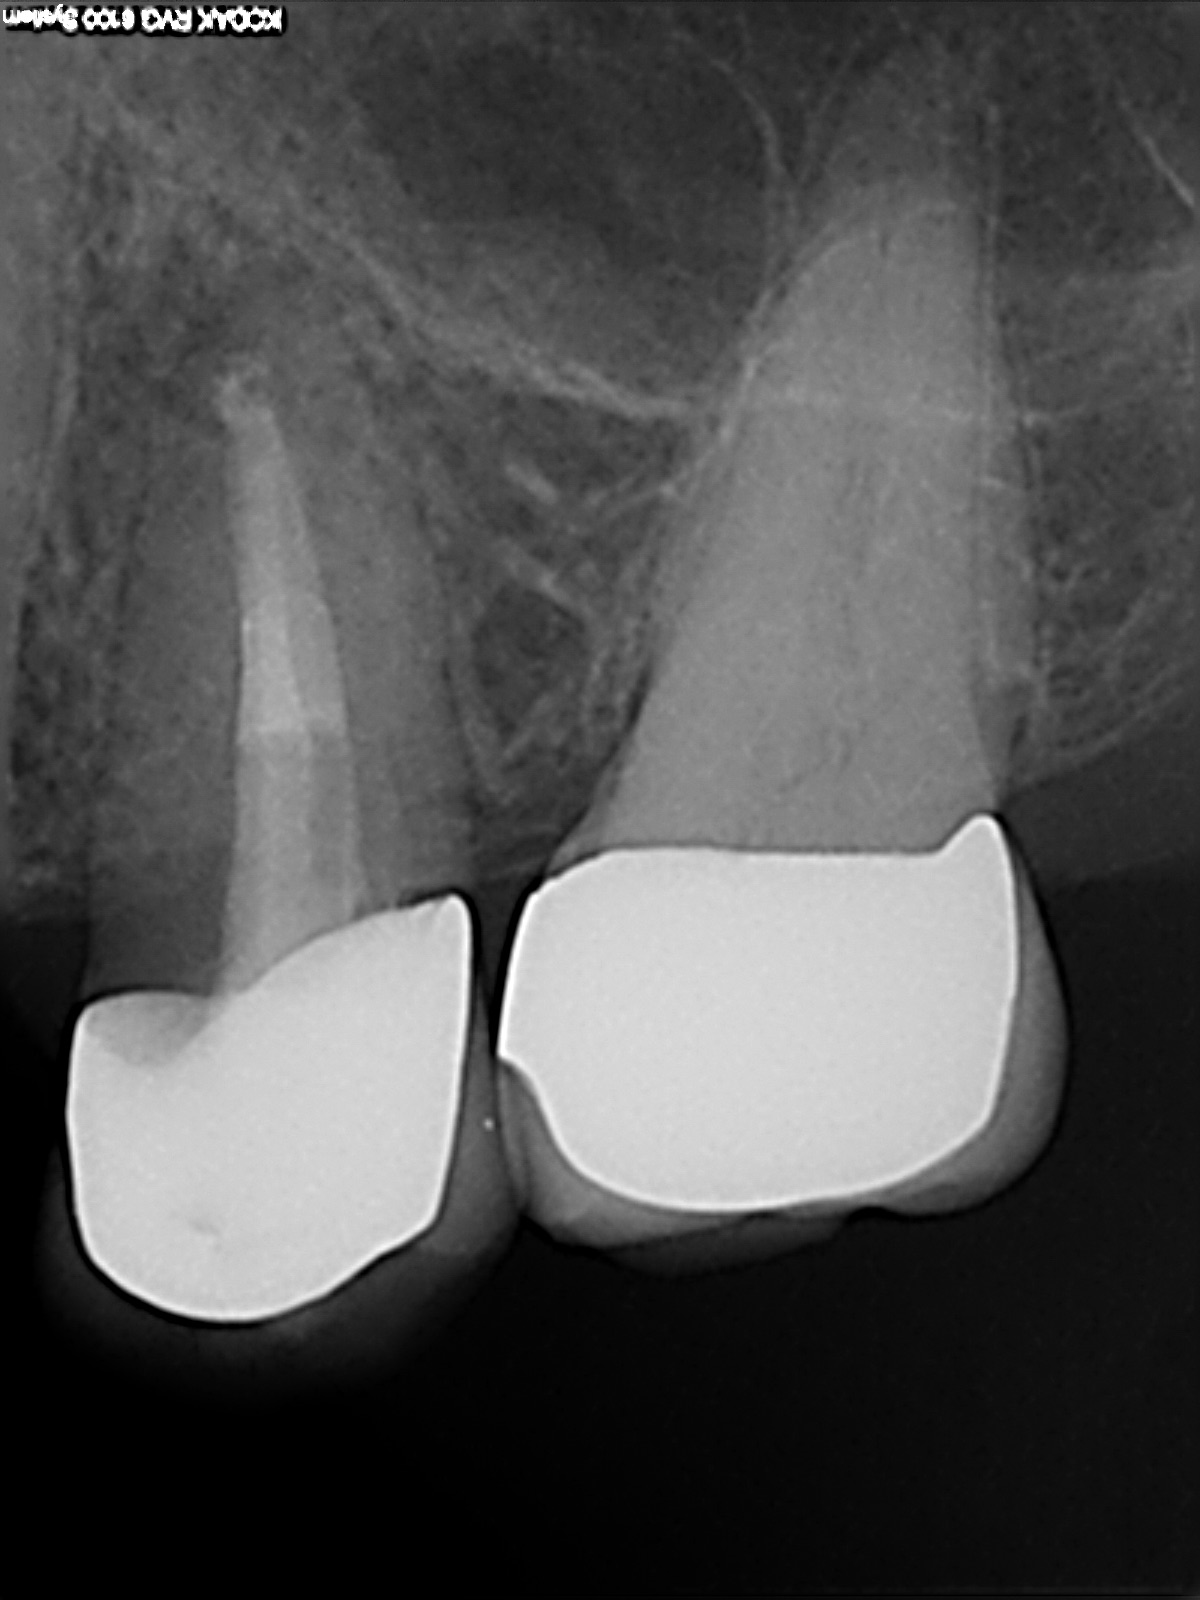

R9

1200 × 1600

Was ist das – Recall

Recall 6 Monate